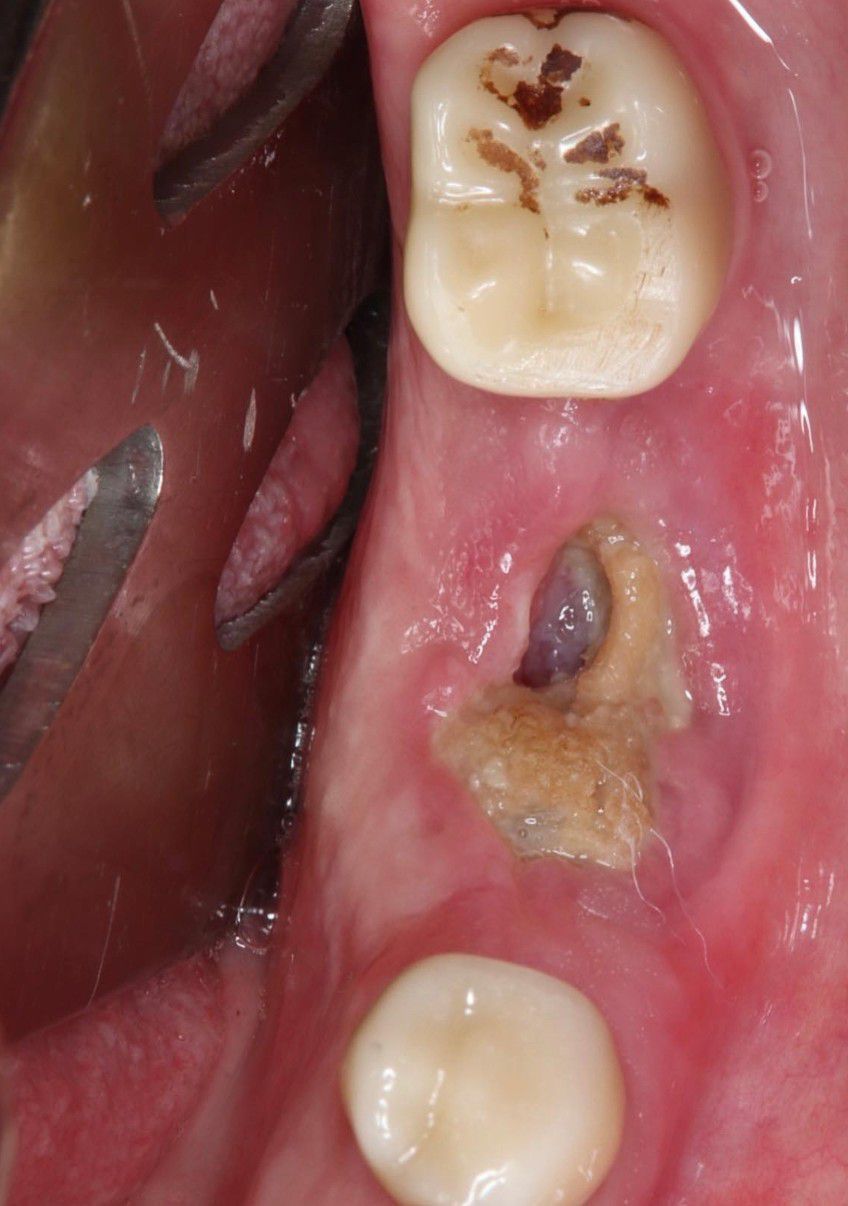

An Update on Management of Medication-Related Osteonecrosis of the Jaw (MRONJ). The AAOMS revised their position paper on MRONJ last year (2022), which is updated from 2014. A few key points: - New meds as risk factors for MRONJ: Tyrosine kinase inhibitors (TKIs such as sunitinib, monoclonal antibodies (bevacizumab), fusion proteins (aflibercept), mTOR inhibitors (everolimus), radiopharmaceuticals (radium 223), selective estrogen receptor modulators (raloxifene) and immunosuppressants (methotrexate and corticosteroids) - Duration of medication therapy DOES NOT significantly increase the risk of MRONJ - Bone turnover markers are NOT validated (ie CTX) for clinical decision making in regards to MRONJ risk - Dental implants should be avoided in cancer patients receiving IV antiresorptive or antiangiogenic medications (not new, necessary reminder) My patient has a history of lung cancer and treated with IV zometa. A few months prior to seeing me, had tooth 19 and implant 20 removed. She subsequently developed stage 2 MRONJ. We started her on pentoxifylline/Vit E for 2 weeks and amoxicillin prior to surgical debridement. We continued PENTE for two weeks post op and augmentin. She is healing beautifully 1 month out with no pain.